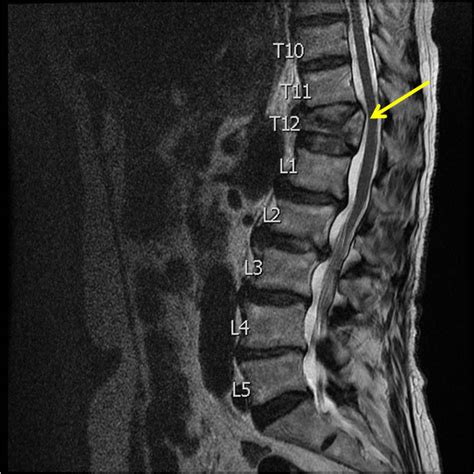

• MRI Scans: MRIs are useful for evaluating soft tissues, such as ligaments and spinal cord. They can help detect nerve compression or other complications.

Imaging tests are crucial for confirming the diagnosis and determining the severity of the fracture.

• X-rays: These are often the first step in evaluating a suspected compression fracture. They can reveal the presence of a fracture and help assess its stability.

• CT Scans: CT scans provide more detailed images of the spine and can help identify subtle fractures or other abnormalities.